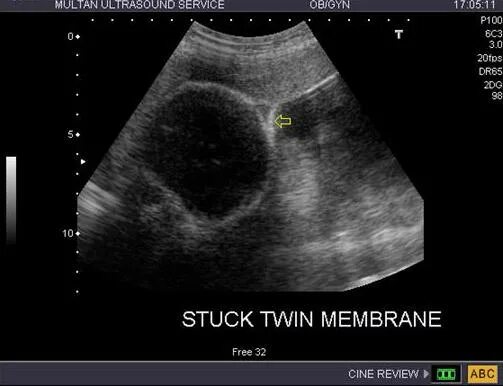

Надпочечник не визуализируется что это значит